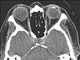

Intraocular foreign body